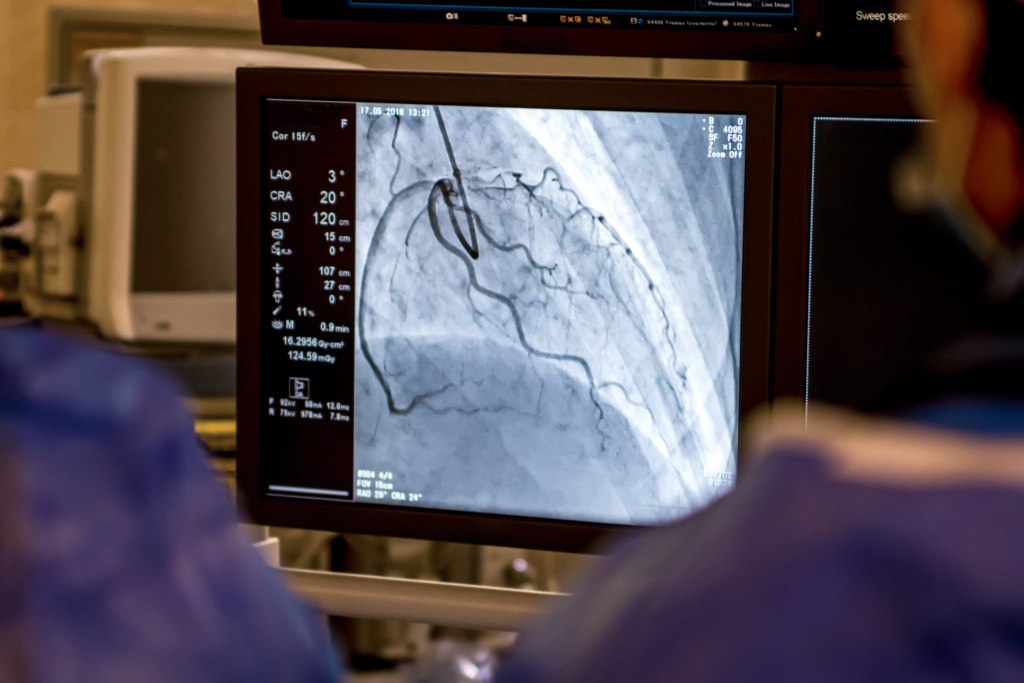

Ангиография – общий термин для рентгенологического исследования сосудов с контрастом, а коронарография – специфический вид ангиографии, который применяется для исследования именно кровеносных сосудов сердца (коронарных артерий). «Ангио» переводится с греческого как «сосуд». Основная функция сосудов – снабжение органов кровью. Ангиография позволяет увидеть проблемные участки сосудов, для этого в просвет сосуда вводится контрастное вещество, отражаемое рентгеновскими лучами. Ангиограф – рентгенологическая установка, предназначенная для проведения исследований и процедур с использованием контрастного вещества и рентгеновского излучения.Сегодня коронарография – одно из самых востребованных диагностических исследований при заболеваниях сосудов сердца. При обнаружении критически значимых поражений (существенного сужения или полной закупорки сосуда тромбом) мы можем тут же оказать помощь пациенту, провести лечение, например выполнить коронарное стентирование (расширить сосуд и поставить стент).

Внутрь кровеносного сосуда вводится очень тонкий диагностический катетер. Ещё десять лет назад катетер вводился через доступ в бедренной артерии, которая имеет достаточно большой просвет и удобна для пункции. Сейчас в нашем отделении почти у всех пациентов используется лучевой доступ – «входим» через лучевую артерию на запястье пациента. Это технически сложнее, поскольку лучевая артерия в несколько раз тоньше, но этот доступ самый безопасный для пациента: риск осложнений минимальный, а жизнеугрожающие ситуации при таком доступе практически исключены..jpg)

Основные показания к коронарографии – ишемическая болезнь сердца со стенокардией высокого функционального класса (то есть возникающая уже при малой физической нагрузке) у пациентов с выраженными нарушениями ритма сердца, острым коронарным синдромом (инфаркт миокарда, предынфарктное состояние), обследование перед некоторыми хирургическими операциями. Коронарография позволяет оценить состояние коронарных артерий, мы хорошо видим анатомию поражения, что даёт возможность с учётом данных других обследований принять обоснованное решение о том, нужно ли хирургическое лечение, и если да, то какие методы лучше использовать.